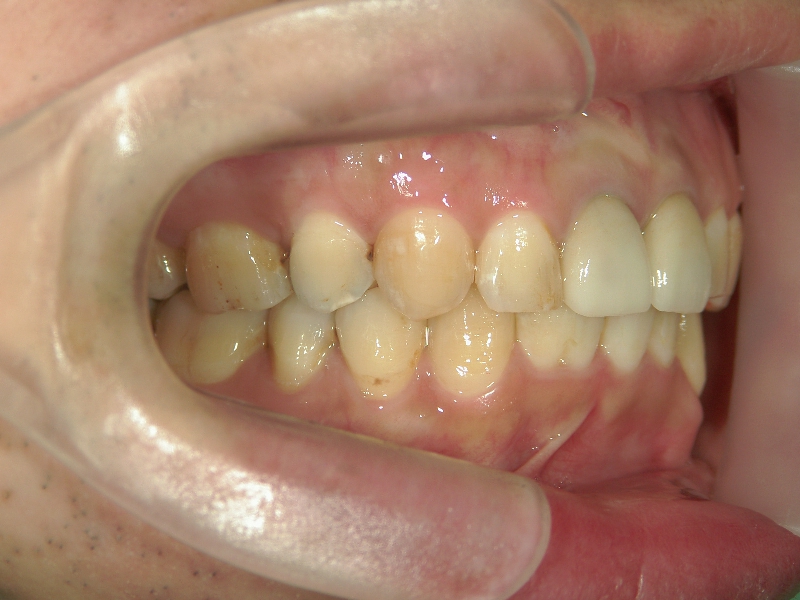

矯正歯科 治療前矯正歯科 治療前

矯正歯科 治療前 上顎の左右4番計2本を抜歯し叢生を改善。